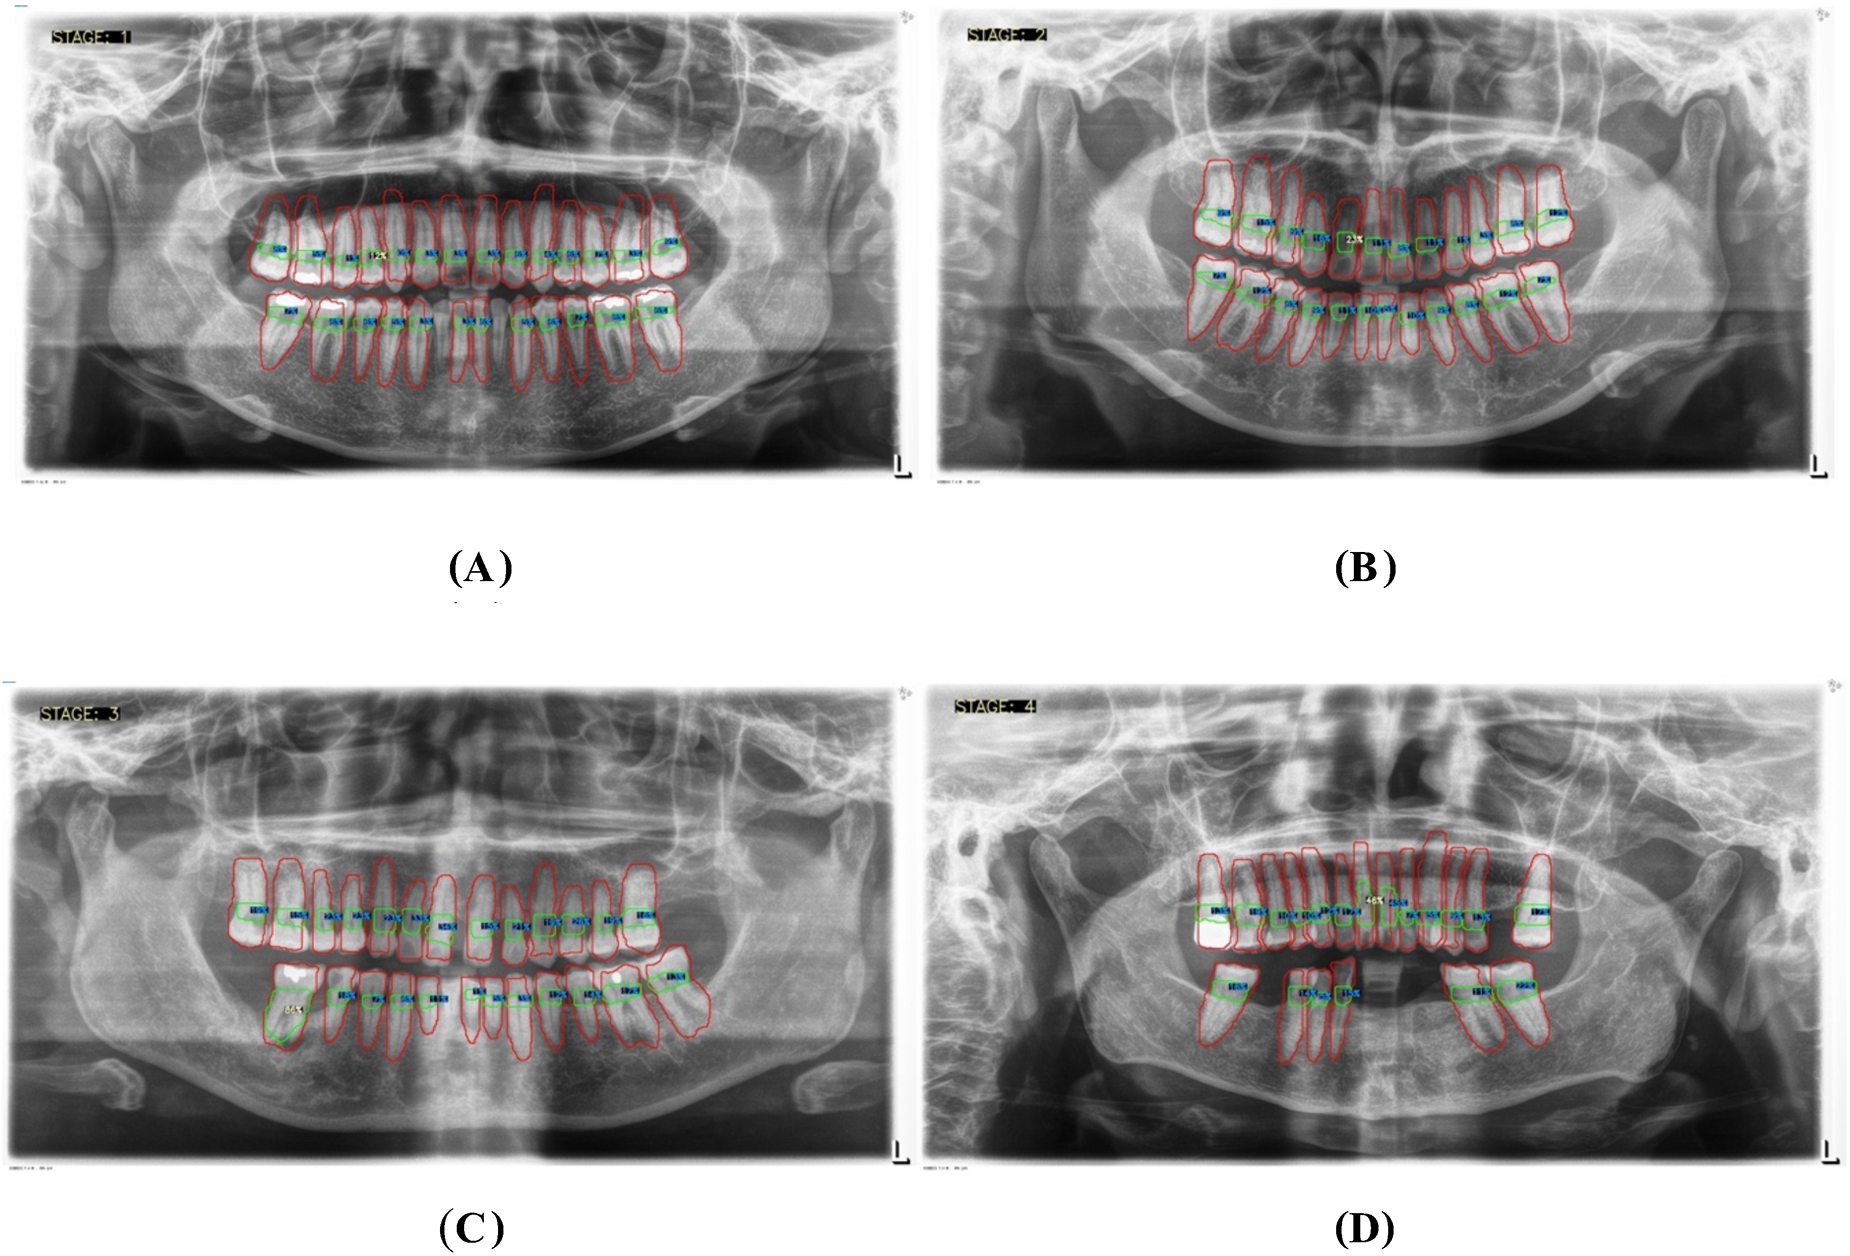

For periodontal diagnosis, the assessments involved calculating the percentage of alveolar bone loss for each tooth in the radiographs. The stage of periodontitis for each patient was determined based on the greatest bone loss observed across all teeth, which was then used to assign the appropriate periodontitis stage as follows (

Figure 7):

- •

Stage I: Bone loss of less than 15% visible in x-rays.

Stage II: Bone loss ranging between 15% and 33% visible in x-rays.

Stage III: Bone loss extending beyond the middle third of the root, with up to 20 teeth remaining.

Stage IV: Similar to Stage III, with bone loss extending beyond the middle third of the root, but with fewer than 20 teeth remaining.

Figure 7

Panoramic x-ray images illustrating the threshold percentages for periodontitis severity: (A) represents stage I, (B) represents stage II, (C) represents stage III, and (D) represents stage IV.